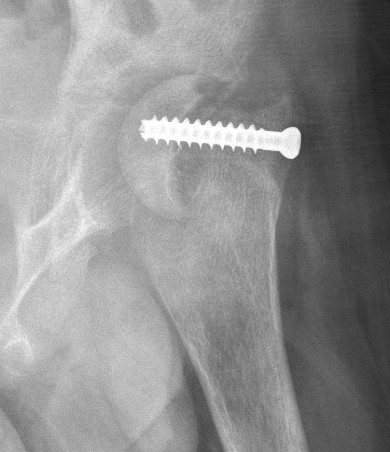

Intertrochanteric / Southwick

Technique

Removal anterolateral bone wedge below lesser trochanter

Valgising / flexion / internal rotation

Base of neck / Kramer

Closing wedge anterior and superior